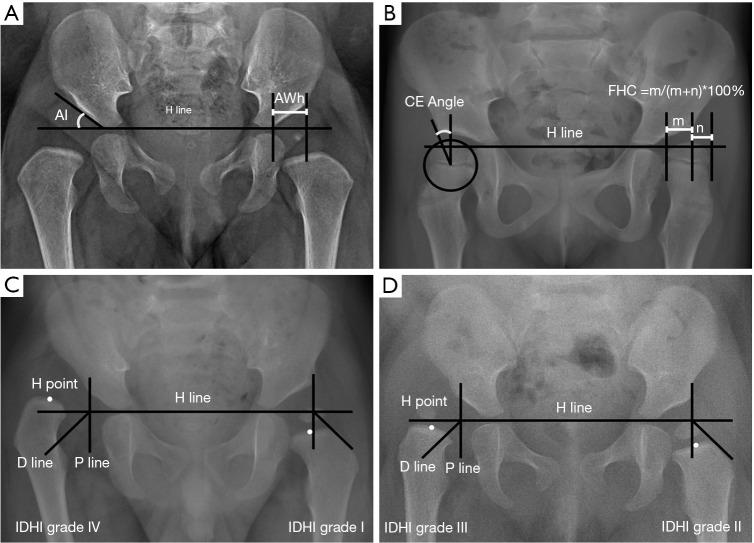

Patients over 12 months of age who underwent successful CR from October 2011 to November 2017 and followed up for at least 2 years were enrolled. Gender, affected side, age at CR and follow-up time were recorded. Acetabular index (AI), horizontal acetabular width (AWh), center-to-edge angle (CEA), and femoral head coverage (FHC) were measured. The cases were divided into two groups according to whether older than 18 months. RHD was determined according to our criteria.

纳入2011年10月至2017年11月期间成功接受CR且随访至少2年的12个月以上患者。记录性别、患侧、CR时年龄及随访时间。测量髋臼指数(AI)、髋臼水平宽度(AWh)、中心边缘角(CEA)和股骨头覆盖率(FHC)。根据年龄是否大于18个月将病例分为两组。根据我们的标准确定RHD。